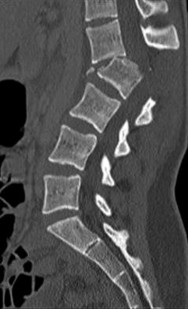

A 35-year-old male construction worker falls 10 feet from scaffolding. He complains of moderate low back pain but has full strength and normal sensation in his lower extremities.

CT imaging shows an L1 burst fracture with 40% loss of anterior vertebral body height and 50% retropulsion into the spinal canal. MRI confirms that the posterior ligamentous complex (PLC) is intact. Based on the Thoracolumbar Injury Classification and Severity (TLICS) score, what is the appropriate score and recommended management?

Explanation

Question 25

A 35-year-old male is involved in a motor vehicle collision. Examination reveals normal motor and sensory function throughout his upper and lower extremities. CT imaging shows an L1 burst fracture with 15 degrees of local kyphosis and 30% canal compromise. MRI confirms an intact posterior ligamentous complex. According to the Thoracolumbar Injury Classification and Severity (TLICS) score, what is the indicated treatment?

A 35-year-old male falls from a ladder and sustains localized thoracolumbar pain. He is neurologically intact. CT and MRI confirm an L1 burst fracture with 15 degrees of kyphosis, 30% canal compromise, and an intact posterior ligamentous complex.

Based on the Thoracolumbar Injury Classification and Severity (TLICS) score, what is the most appropriate management?